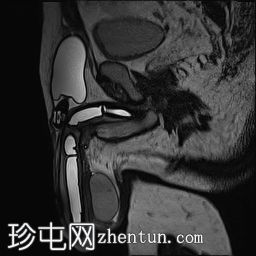

矢状位

T2加权像

MRI显示可充气式阴茎假体位于体内。

假体柱体对称地位于阴茎海绵体内,并沿其走行方向完全扩张。

未见海绵体破裂或假体柱体断裂的迹象。

泵储液囊位于阴囊内,位置正常。

阴囊壁皮下可见轻度水肿,但无明显积液,可能为反应性水肿。

储液囊位于右侧腹股沟管前方的皮下脂肪内,对右侧腹直肌施加轻微的向上压迫,周围有少量积液。这些发现最符合术后改变。

在本病例中,MRI显示假体圆柱体位置正常,无破裂或不连续的迹象。储液囊和泵的位置也正确。周围轻微的水肿和积液可能是术后改变。因此,患者的症状可能与机械刺激或装置相关的机械因素有关,而不是假体的结构性故障。